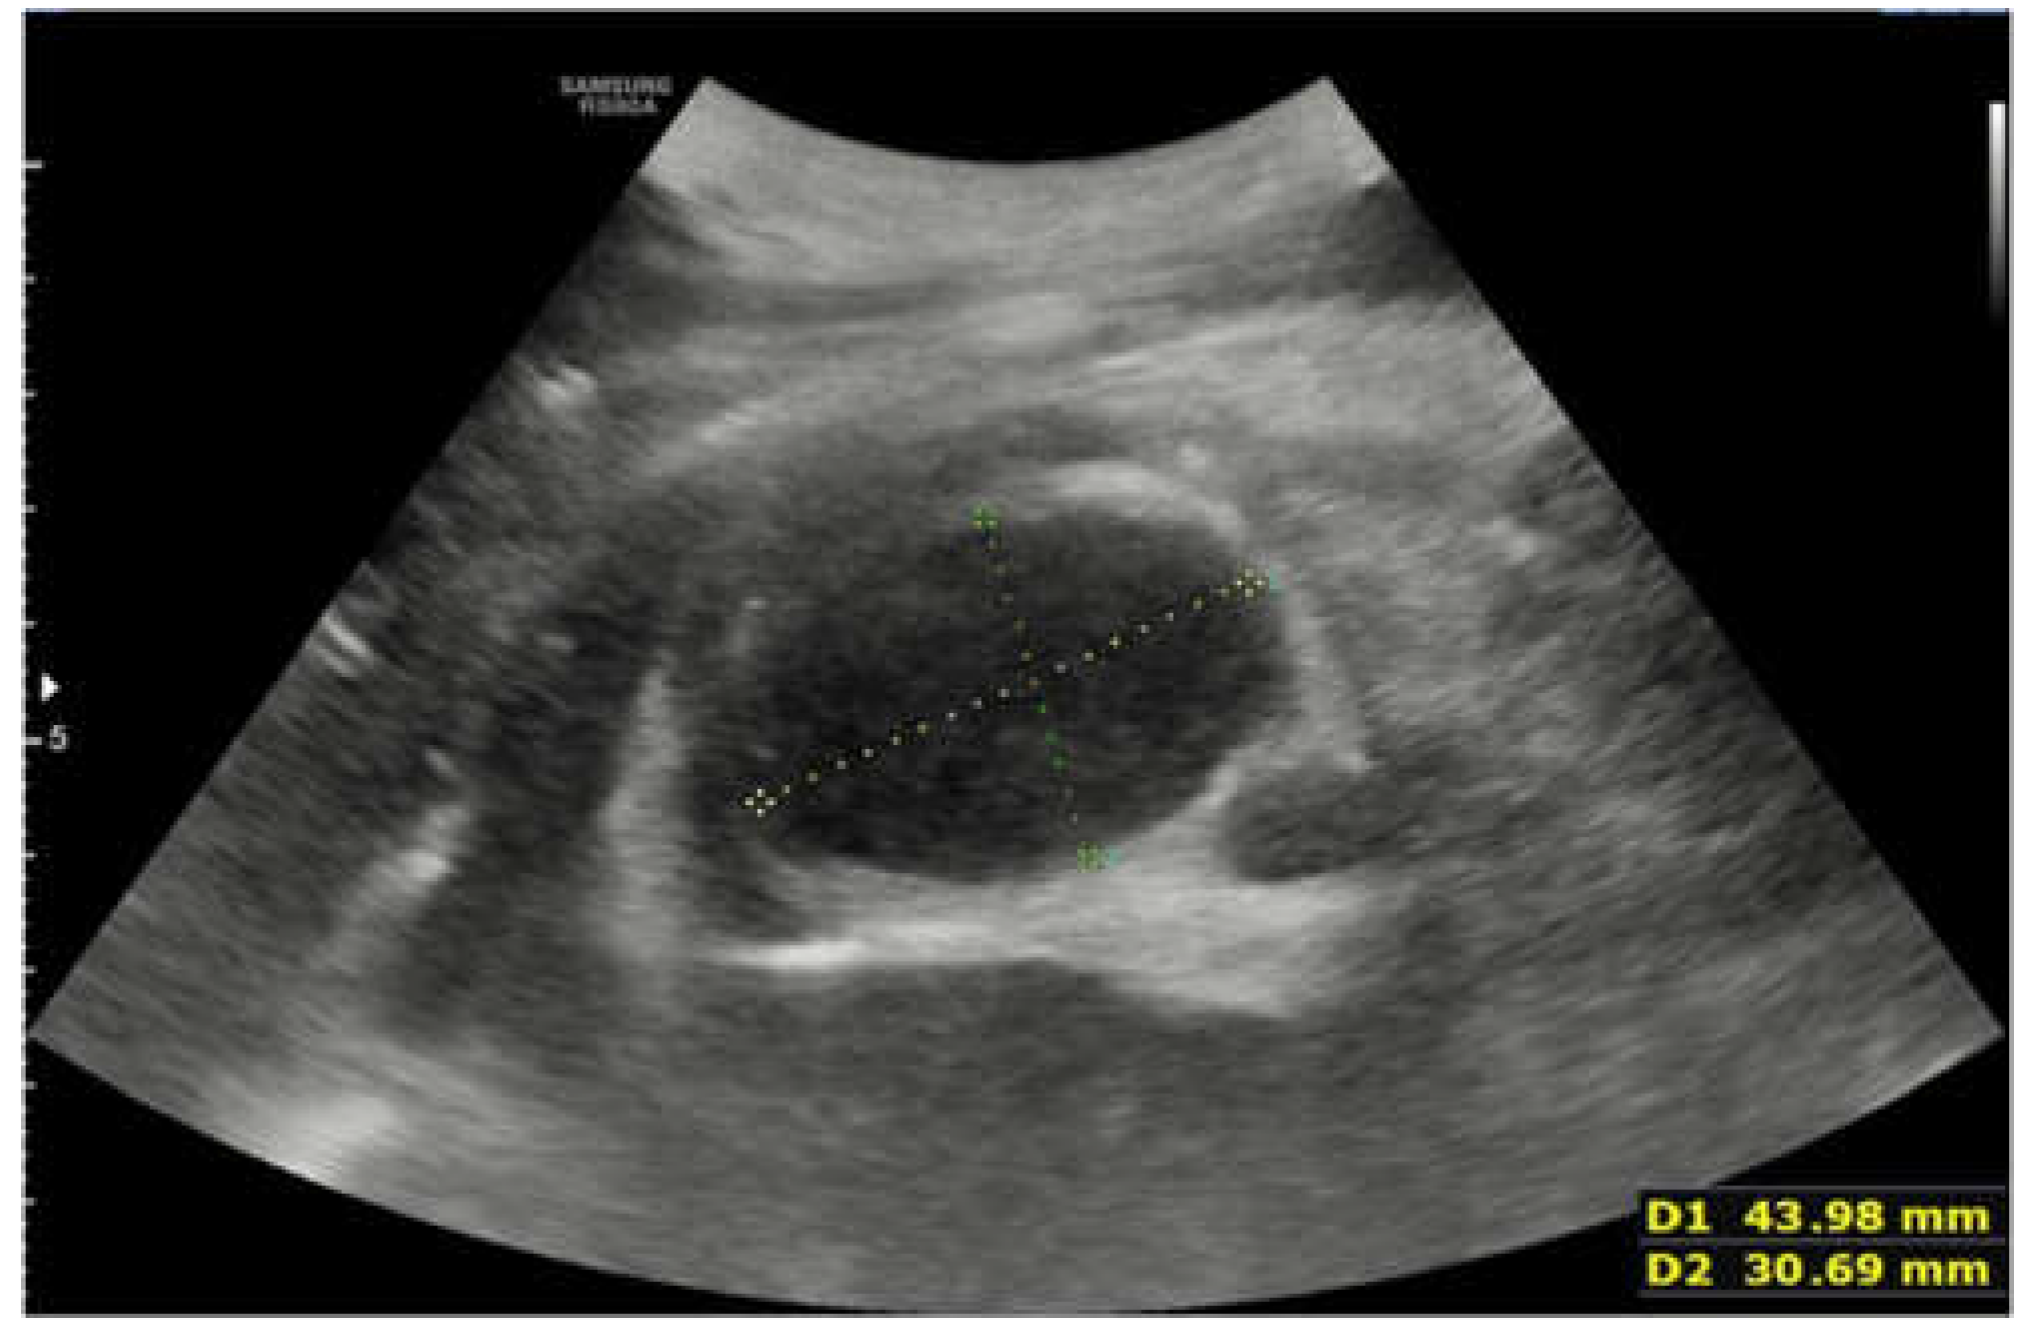

The Key Role of Lung Ultrasound in the Diagnosis of a Mature Cystic Teratoma in a Child with Suspected Difficult to Treat Pneumonia: A Case Report

2. Case Report